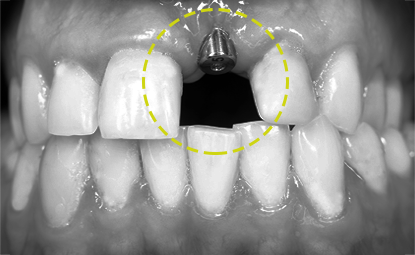

잇몸뼈의 상태 확인

잇몸뼈에 치아 뿌리를 대체할 티타늄을 식립하는 임플란트는 만일 앞니 임플란트를 시술할 부위에 잇몸뼈가 퇴축되어 있다면 앞니 임플란트 최종결과에 심미적 단점을 만들 수 있습니다. 이런 경우 사전에 잇몸뼈 이식 수술을 통해 잇몸뼈를 보강한 후 앞니 임플란트를 시술하면 심미성이 개선될 수 있습니다.

충분한 잇몸뼈

앞니는 다른 부위에 비해 잇몸폭과 뼈가 좁고 얇기 때문에 정확한 진단이 필요합니다. 잇몸뼈의 양이 부족한 경우 잇몸이 꺼져 보일 수 있어 뼈이식을 병행하는 것이 좋습니다. 또한 임플란트 식립 후 잇몸뼈가 흡수 되는 것을 고려하여 시간이 지나도 충분히 미적인 앞니의 모양이 지속 될 수 있도록 시술 되어야 하며, 오랜 기간 동안 꾸준히 관리가 이루어 질 수 있도록 해야 합니다.

건강한 잇몸

앞니는 치아뿐만 아니라 잇몸까지도 가지런하게 시술 되어 져야 심미적으로 성공적인 임플란트라고 할 수 있습니다. 앞니 임플란트는 잇몸의 상태에 따라 치아 길이나 폭, 모양이 달라 질 수 있기 때문에 임플란트 식립시 착오가 없도록 식립 위치와 방향, 경사각도, 깊이 등을 세심하게 파악하여 정밀한 치료계획이 필요합니다. 건강한 잇몸은 건강한 앞니 임플란트 시술의 첫째 조건 입니다.